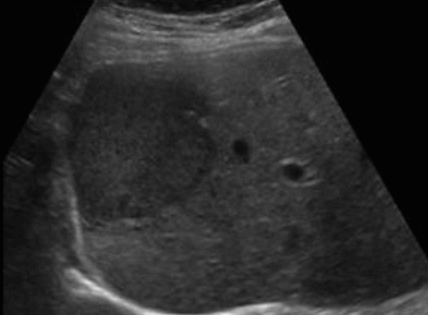

hepatocellular adenoma (간세포선종) US finding

- 원형의 저에코, 등에코, 고에코등의 종괴로 다양하다.

- 피막을 갖는다

- 크기가 8~14cm으로 크다

- 간전이암이나 간세포암과 정확히 구별이 어렵다.

- hypoechoic rim (띠가 혈관이다)

- usually solitary and heterogeneous